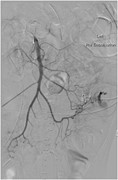

Anterior knee pain: an unusual presentation of renal cell carcinoma

John Broomfield and others

Journal of Surgical Case Reports, Volume 2014, Issue 3, March 2014, rju018, https://doi.org/10.1093/jscr/rju018